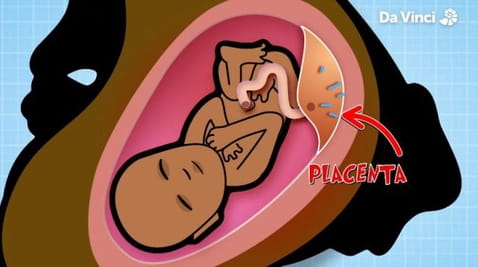

1. Mamy dziecko